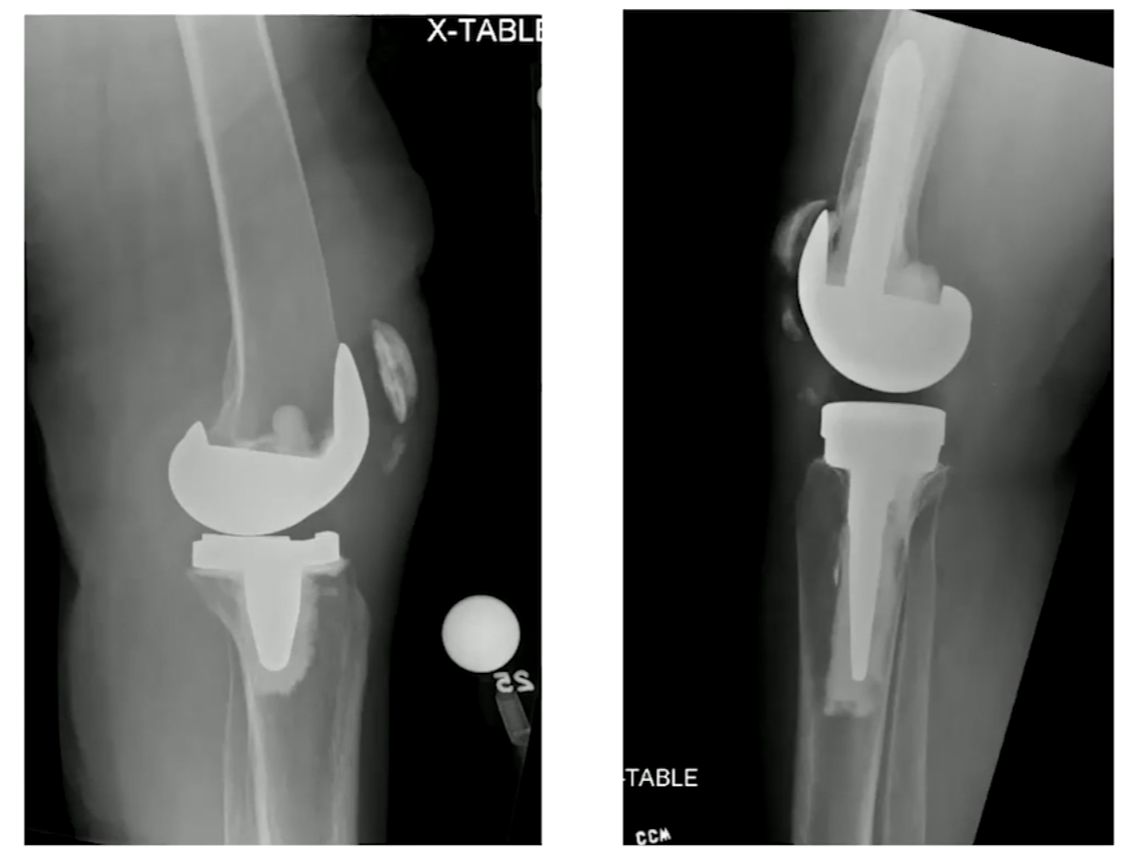

정형외과 전문적인 내용 입니다. 20년 전에 쓰여진 논문으로 슬개골에 골절이 생긴 경우 type을 3가지로 나누어 수술을 진행하도록 합니다. 만 케이스중에 0.68% 정도 있으니 많은 수는 아닙니다.

Type I, II, III 로 나뉠 수 있는데 모두 intact한 경우 I, implant는 intact하나 extensor mechanism이 작동하지 않을 때는 II, implant도 loosening 되고, implant 도 풀린 경우에는 III 로 나뉠 수 있습니다.

Type I 이 가장 흔한 케이스로, 수술을 안하고 지켜볼 수 있습니다. 6주간의 편 상태에서 immobilization 을 합니다. patella fracture의 경우 한번의 굽힘 등으로 크게 골절이 벌어질 수 있기 때문에 Cast apply를 주로 하는 편 입니다.

무릎 인공관절 중에 슬개골 치환술을 안하는 경우도 있는데 골절의 정도에 따라 수술 없이 경과관찰 해볼 수 있습니다.